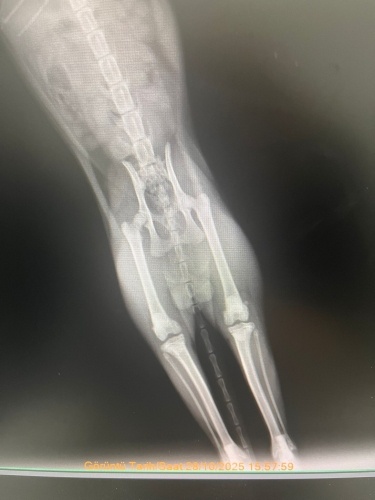

Merhabalar, sekiz aylık kedimin yüksekten düşme sebebiyle sağ arka bacagı kırıldı. Veterinerimiz bir haftalık kafes istirahati ve kalsiyum takviyesi ile kayanayabilecegini söyledi. Hem genç oldugu için hemde kırık çok ayrılmadıgı için. Kalsiyum kaici kedi yogurdu, vitamin malt, kemik iliği suyuyla destekliyorum. Ödül mamalarını falan reddetmiyor mamasını da yiyor ama suyun yüzüne bile bakmıyor. Kaşıkla diline bırakıyorum öyle içiyor. Başına gelen var mı bilmiyorum ama hem kırıkla ilgili yorum hemde su konusunda tavsiyesi olan var mıdır? Fotograf ekliyorum